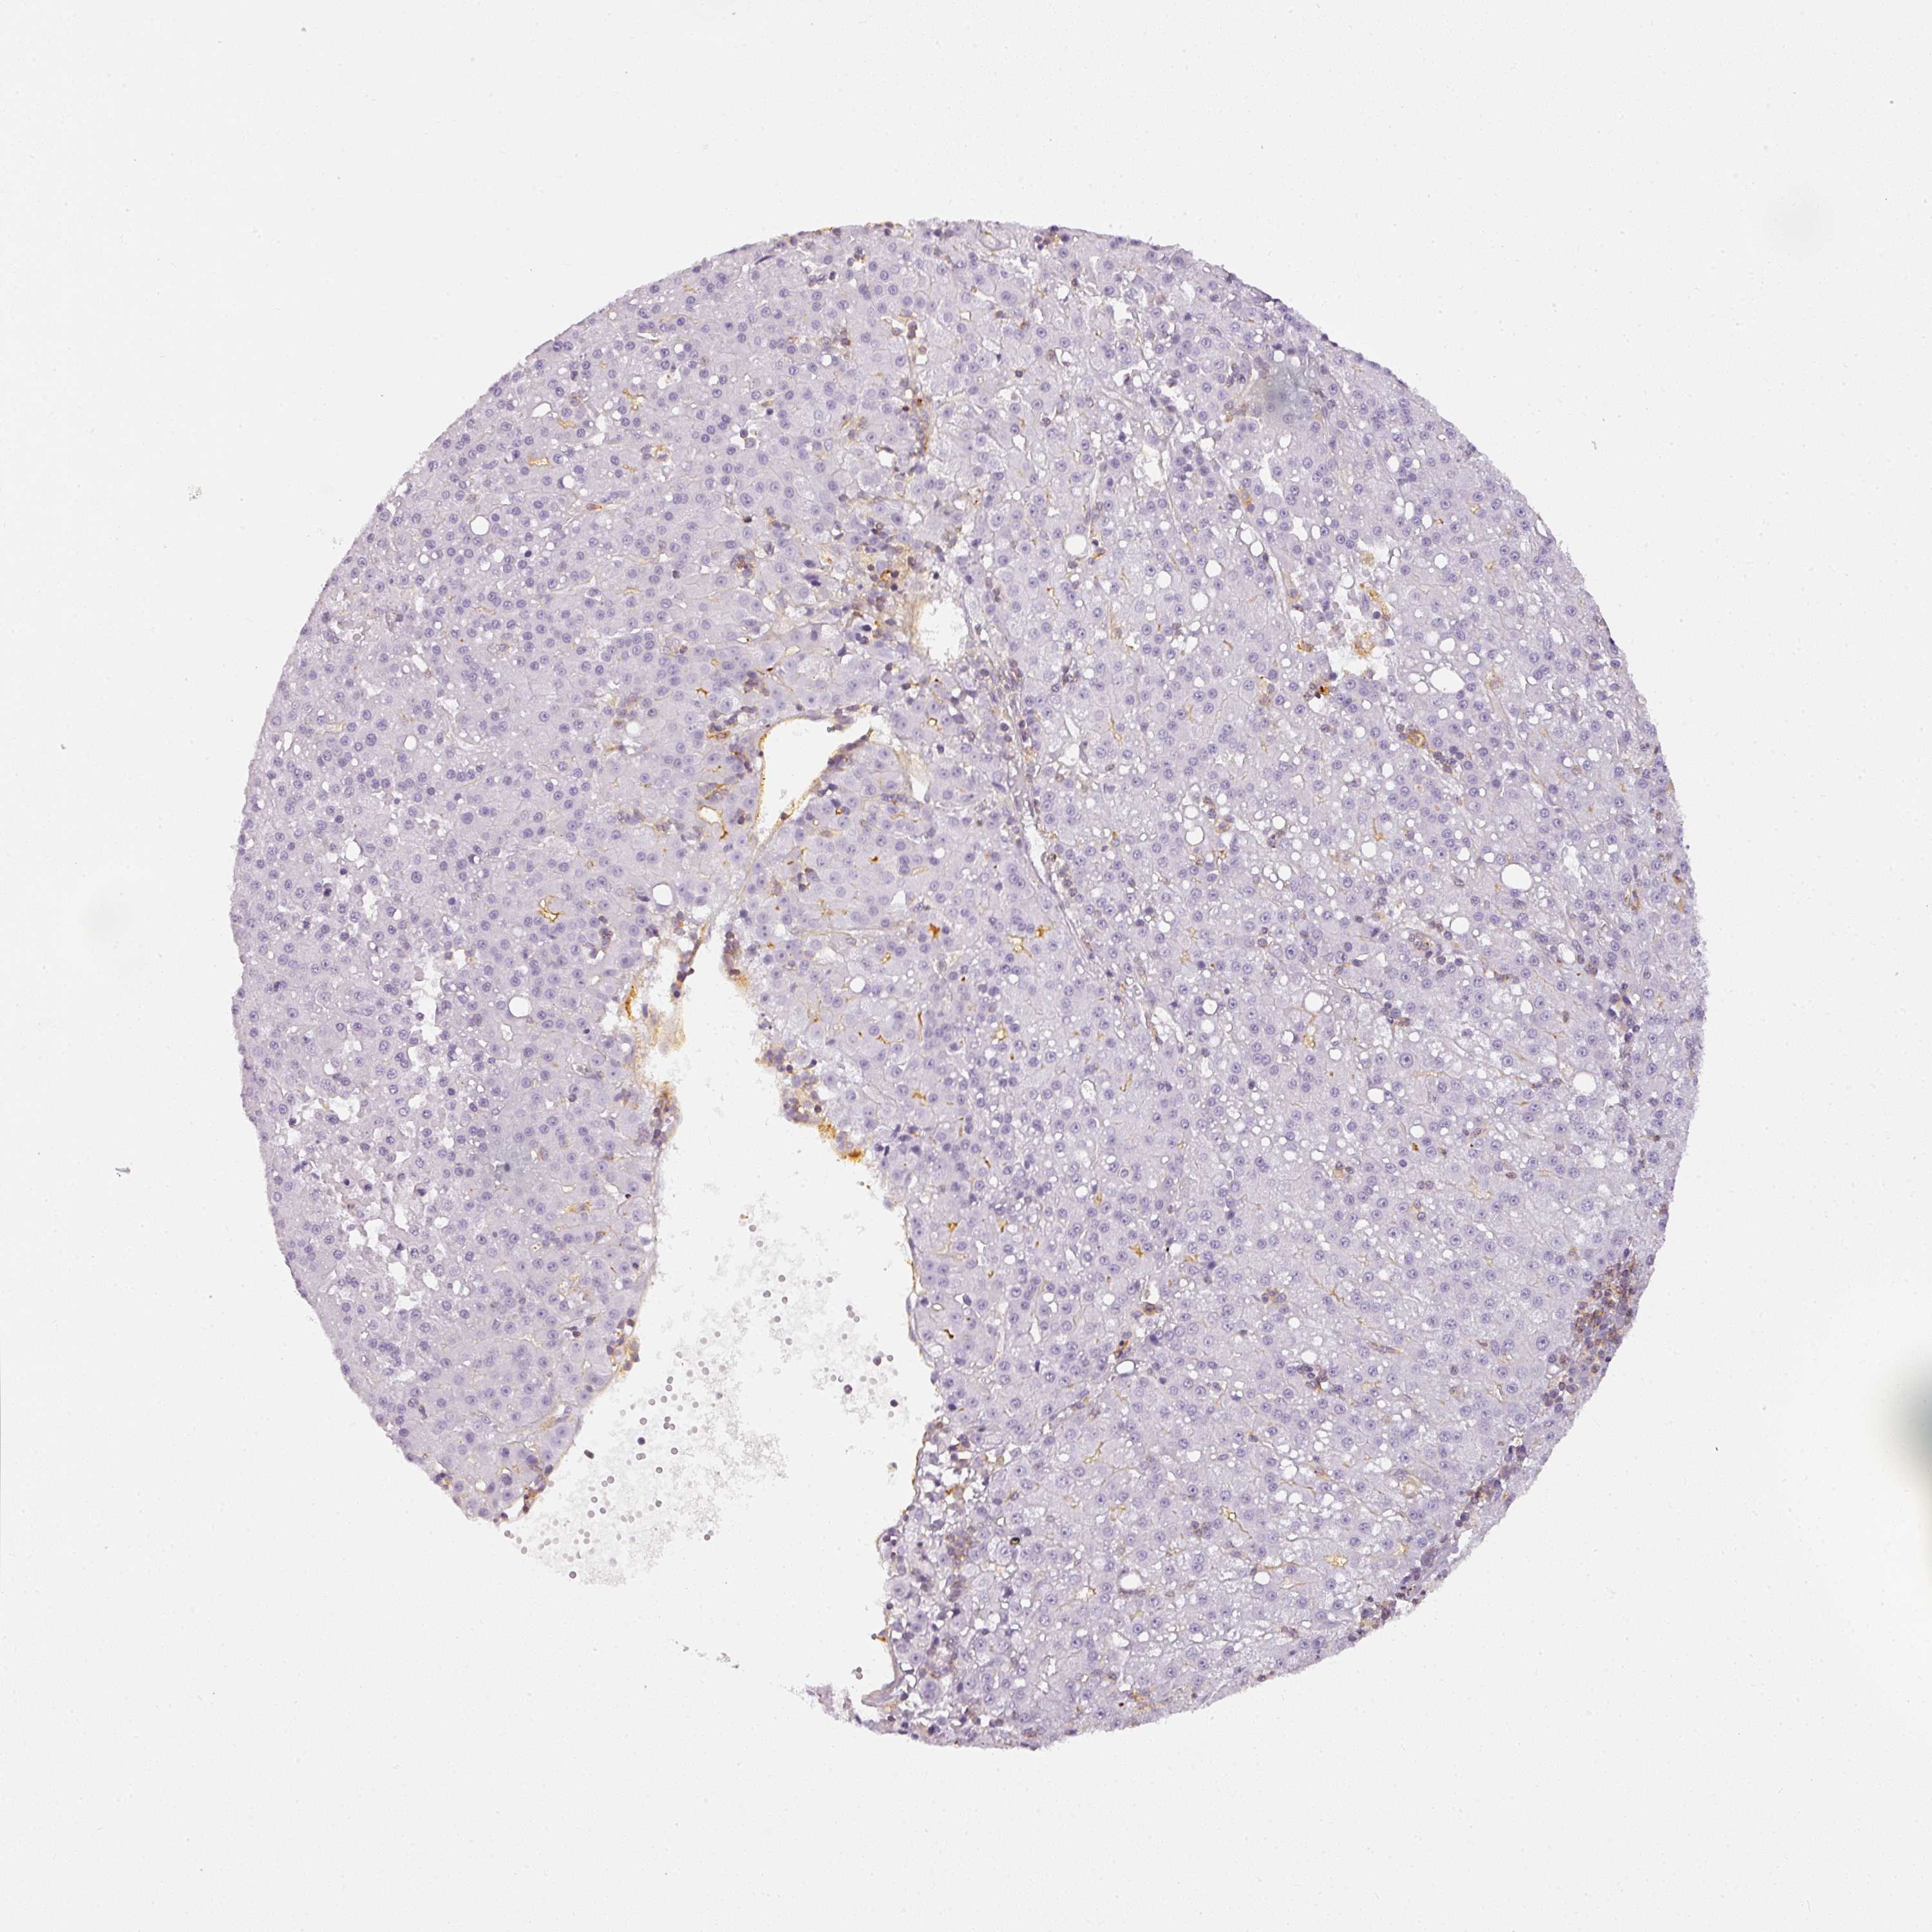

LIVER CANCER - Protein expressioni

A mouse-over function shows sample information and annotation data. Click on an image to view it in a full screen mode. Samples can be filtered based on level of antibody staining by selecting one or several of the following categories: high, medium, low and not detected. The assay and annotation is described here.

Note that samples used for immunohistochemistry by the Human Protein Atlas do not correspond to samples in the TCGA dataset.

Antibody stainingi

Antibody staining in the annotated cell types in the current human tissue is reported as not detected, low, medium, or high, based on conventional immunohistochemistry profiling in selected tissues. This score is based on the combination of the staining intensity and fraction of stained cells.

Each image is clickable and will lead to virtual microscopy that enables deeper exploration of all samples and also displays staining intensity scores, fraction scores and subcellular localization as well as patient and tissue information for each sample.

Antibody HPA052569

Staining

High

Medium

Low

Not detected

Intensity

Strong

Moderate

Weak

Negative

Quantity

>75%

75%-25%

<25%

None

Location

Nuclear

Cytoplasmic/membranous

Cytoplasmic/membranous,nuclear

Carcinoma, Hepatocellular, NOS

Cholangiocarcinoma